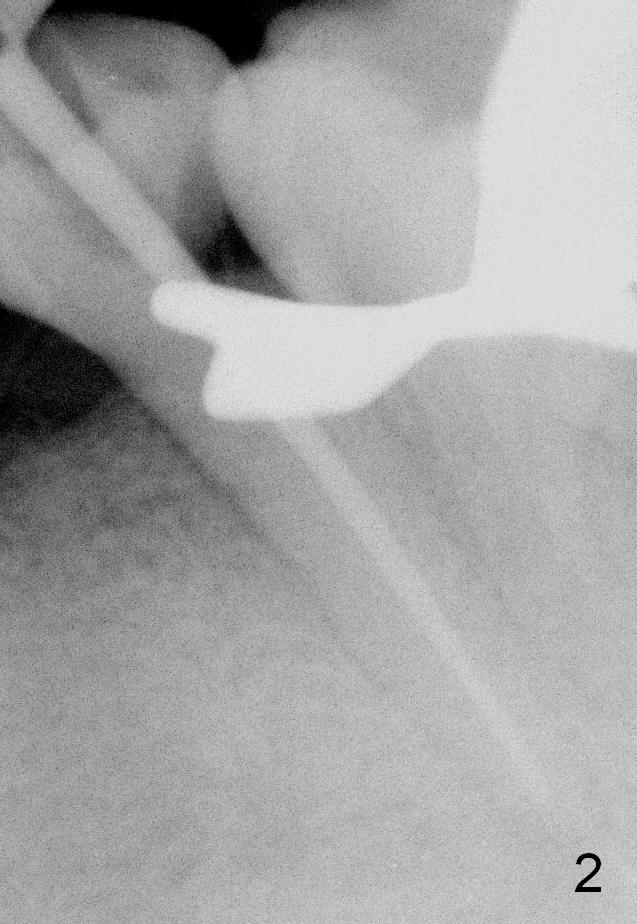

CT sagittal section of a similar case shows that the root is also long, but curved (Fig.4).  A 4.5x14 mm implant is slightly longer than the root.  The apex of the implant has distance to the underlying nerve (N).  The coronal section shows that the implant should be placed lingually (Fig.5 L), since the buccal (B) plate is thin (Fig.6 between arrowheads).  The first drill (2 mm) is to be placed lingually (Fig.7 red arrow).  When the implant is placed, there should be a buccal gap, to be filled with bone graft (Fig.5 red circles).